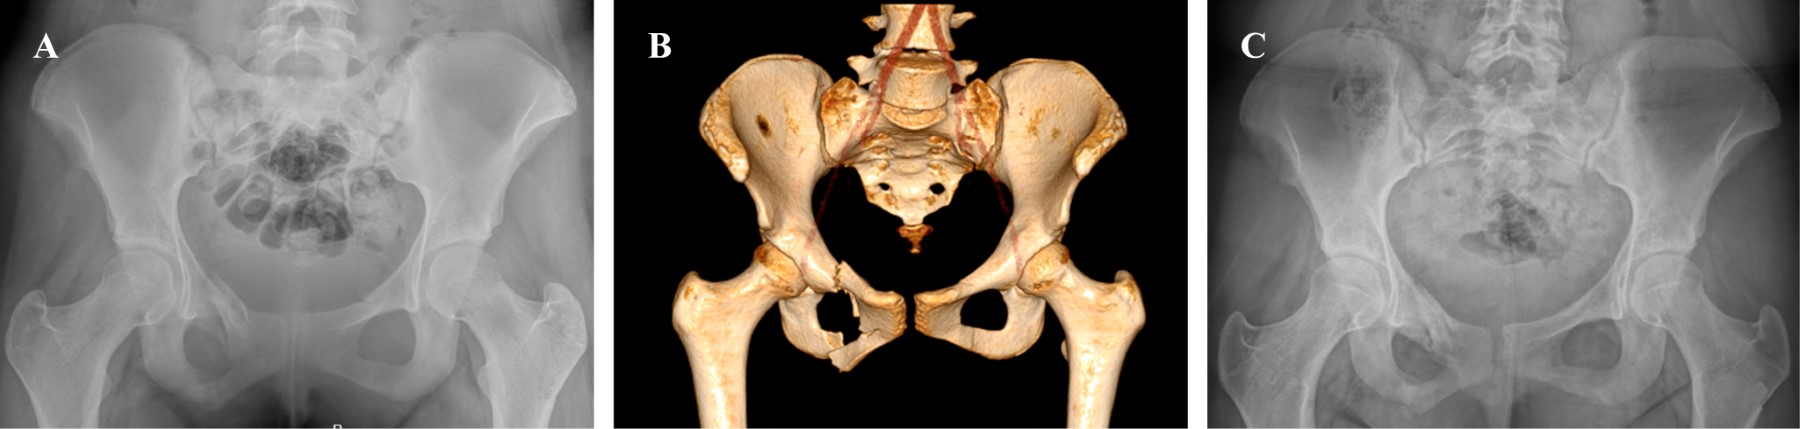

Figure 1

Clinical and functional evaluation of pediatric patients with pelvic fracture treated in a third level Hospital